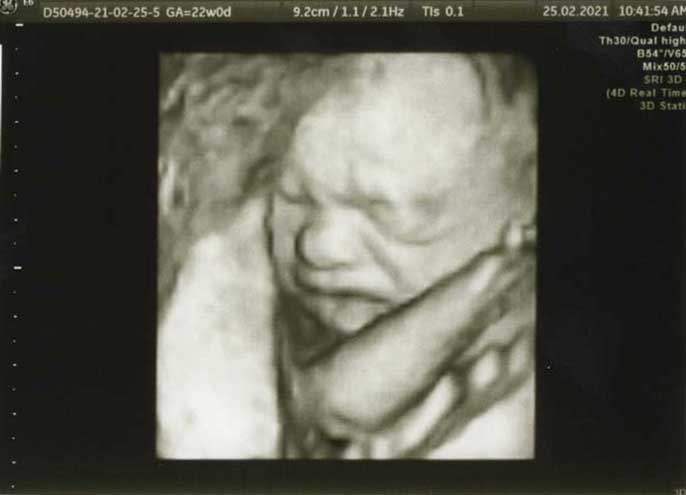

3D/4D HD LIVE

Στο ιατρείο μας προσφέρουμε υψηλής ευκρίνειας 3D και 4D τεχνολογία απεικόνισης του εμβρύου. Η τεχνολογία αυτή αποτελεί ένα ακόμα σημαντικό διαγνωστικό όπλο στη φαρέτρα του προγεννητικού ελέγχου, ενώ ταυτόχρονα ενισχύει την ανάπτυξη του δεσμού ανάμεσα στους μελλοντικούς γονείς και το μωρό τους.